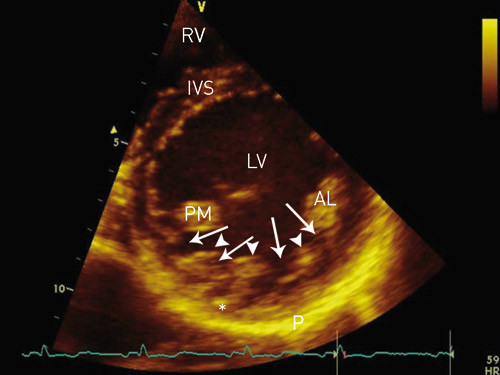

Left-ventricular noncompaction (LVNC) has been reported in fewer than 1 % of patients in various echocardiographic studies, and may exist as a familial disposition. The condition arises from an arrest in normal myocardial embryogenesis (1) and has recently been described as a cause of left-ventricular dysfunction (1) – (6). Affected children and adults may develop heart failure, thromboembolic events, and/or ventricular arrhythmias (1, 2, 7) – (9). Two-dimensional echocardiography or magnetic resonance imaging (MRI) of the heart is used to diagnose the condition (5, 7, 9) – (12). Typical findings include a thin, normally developed outer layer of the left- ventricular myocardium, and an inner layer (closest to the endocardium) thickened by trabeculae with deep intertrabecular recesses (fig 1).

During embryogenesis, the mesh of muscle fibres making up the heart normally becomes compacted while the intertrabecular sinusoids degenerate. This compaction process occurs in gestational weeks 5 – 8, and results in transformation of intertrabecular sinusoids to capillaries. It starts in the epicardium and progresses inward towards the endocardium, from the base of the heart to apex, and is more complete in the left ventricle (LV) than in the right ventricle (RV). Development of the coronary circulation occurs in the same period (1, 13) and is inhibited in the presence of noncompaction. The result is multiple persistent and prominent ventricular trabeculae, and deep intertrabecular recesses which communicate with the ventricular cavity and not with the coronary circulation (fig 1, fig 2). The ventricular cavity and the intertrabecular recesses are covered by a continuous endothelium (1, 2, 5). Predilection sites for noncompaction (normal findings in fish, amphibian and reptile hearts [4]) are the mid and distal segments of the lateral and inferior walls, as well as in the apical region (5, 9, 13). The extent of changes varies among patients (1, 4).

Several echocardiographic findings are considered to be typical (2, 5, 7, 9) – (11):

Absence of other cardiac anomalies (by definition).

Involvement of the apex and/or apical and/or midventricular segments of the inferior and/or lateral wall. More than 80 % of patients with LVNC display noncompaction in one or more of these predilection sites.

Three or more prominent myocardial trabeculae in the same image plane.

Deep intertrabecular recesses that communicate with the ventricular cavity.

The affected myocardial segments have two layers: a thin epicardial layer and a thickened trabecular endocardial layer.

The outer myocardial layer is compacted in a normal way, but the inner layer is noncompacted. When the wall segments are measured at end-systole, the relationship between the noncompacted layer and the compacted layer will typically be > 2.0.